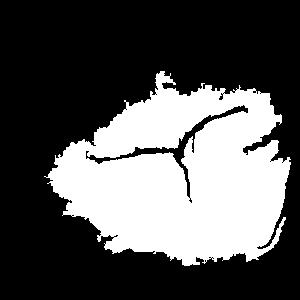

Figure 2a. illustrates the information retrieved from this CNN model from various layers of the architecture that is used to create a BAM map, which is used to segment the burn injury from normal skin in a 2D image. First, the heatmaps for the activations of the first convolutional layer are computed (Figure 2a(ii)), and then Grad-CAM heatmap is computed using the last convolutional layer (Figure 2a(iii)). Once the first convolutional layer heatmaps and Grad-CAM are generated, the algorithm uses a three-round iterative process to select activation heatmaps that have the highest correlation to the Grad-CAM heatmap among the channels of the first layer activations. After the process of correlating and selecting heatmaps is completed (Figure 3 ), segmentation masks are created next (Figure 4). A final composite BAM mask is created as illustrated in 2b(i). Finally, figure 2b (ii-iii) illustrates how the BAM mask is superimposed on the input image to segment the burn injury area, and how edge detection may be applied to the BAM mask in order to obtain a fine-tuned segmented boundary superimposed on the input image.

Figure 3 and Algorithm 1 detail the iterative process that is used to select the activation channel heatmaps and Grad-CAM, by the algorithm. For the example burn image, the first iteration of the algorithm selects channel since it has the highest correlation to the Grad-CAM heatmap among the channels of the first layer activations, as given by the Spearman’s correlation coefficient, . The second iteration selects channel to be added to the combination since averaging it with channel results in the highest increase in the correlation value with the Grad-CAM heatmap. Finally, the third iteration adds channel to the combination of channels and .

Once the heatmaps with the highest correlation coefficients are selected, these high-resolution visualizations are utilized as the input to make binary segmentation masks as illustrated in Figure 4(i). The generation of masks uses Gaussian components of the maps to find thresholds (Figure 4(ii)) and subsequently uses the highest Intersection-Over-Union (IOU) values (Figure 4(iii)) between the binary masks generated and the Grad-CAM to select the final mask. The generated binary segmentation mask lastly undergoes a post-processing step in order to filter out the noise/false positive regions and produce the final BAM mask (Figure 4(iv)), which can be used for super-positioning on the input image (Figure 2b).

Figure 5 shows several burn image examples of patients with different sized burns in different body locations, for which the Grad-CAM heatmap, BAM heatmap, BAM masks, and final superimposed images were created. These results allow us to understand the clinical accuracy of burn segmentation from 2D images using BAM. These images show various degrees of burn. It is evident from the results that given skin burn images and the corresponding Grad-CAM heatmaps highlighting the burn regions even partially, the BAM heatmap is able to highlight the burn regions and display a high resolution heatmap accurately. This is the main contribution of BAM. It can be seen from the figure that the BAM heatmaps display different contrast levels in highlighting the burn regions. More precisely, the more superficial burns are highlighted with a lower contrast to the normal skin. The deeper burns, on the other hand, are highlighted with a higher contrast to the normal skin. Nevertheless, the contrast between the burn regions and the normal skin in the BAM heatmaps is sufficient for generating the binary segmentation masks even for the more superficial burns. As evidenced, the BAM heatmaps can successfully be converted into accurate binary segmentation masks. The rightmost column of the figure shows the BAM segmentation masks on top of the input images in order to better visualize the effectiveness of BAM in segmenting the burn regions. In short, comparing the Grad-CAM heatmaps against the BAM heatmaps and BAM segmentation masks provides evidence for a significant improvement in generating heatmaps that are both class-discriminative and fine-grained.